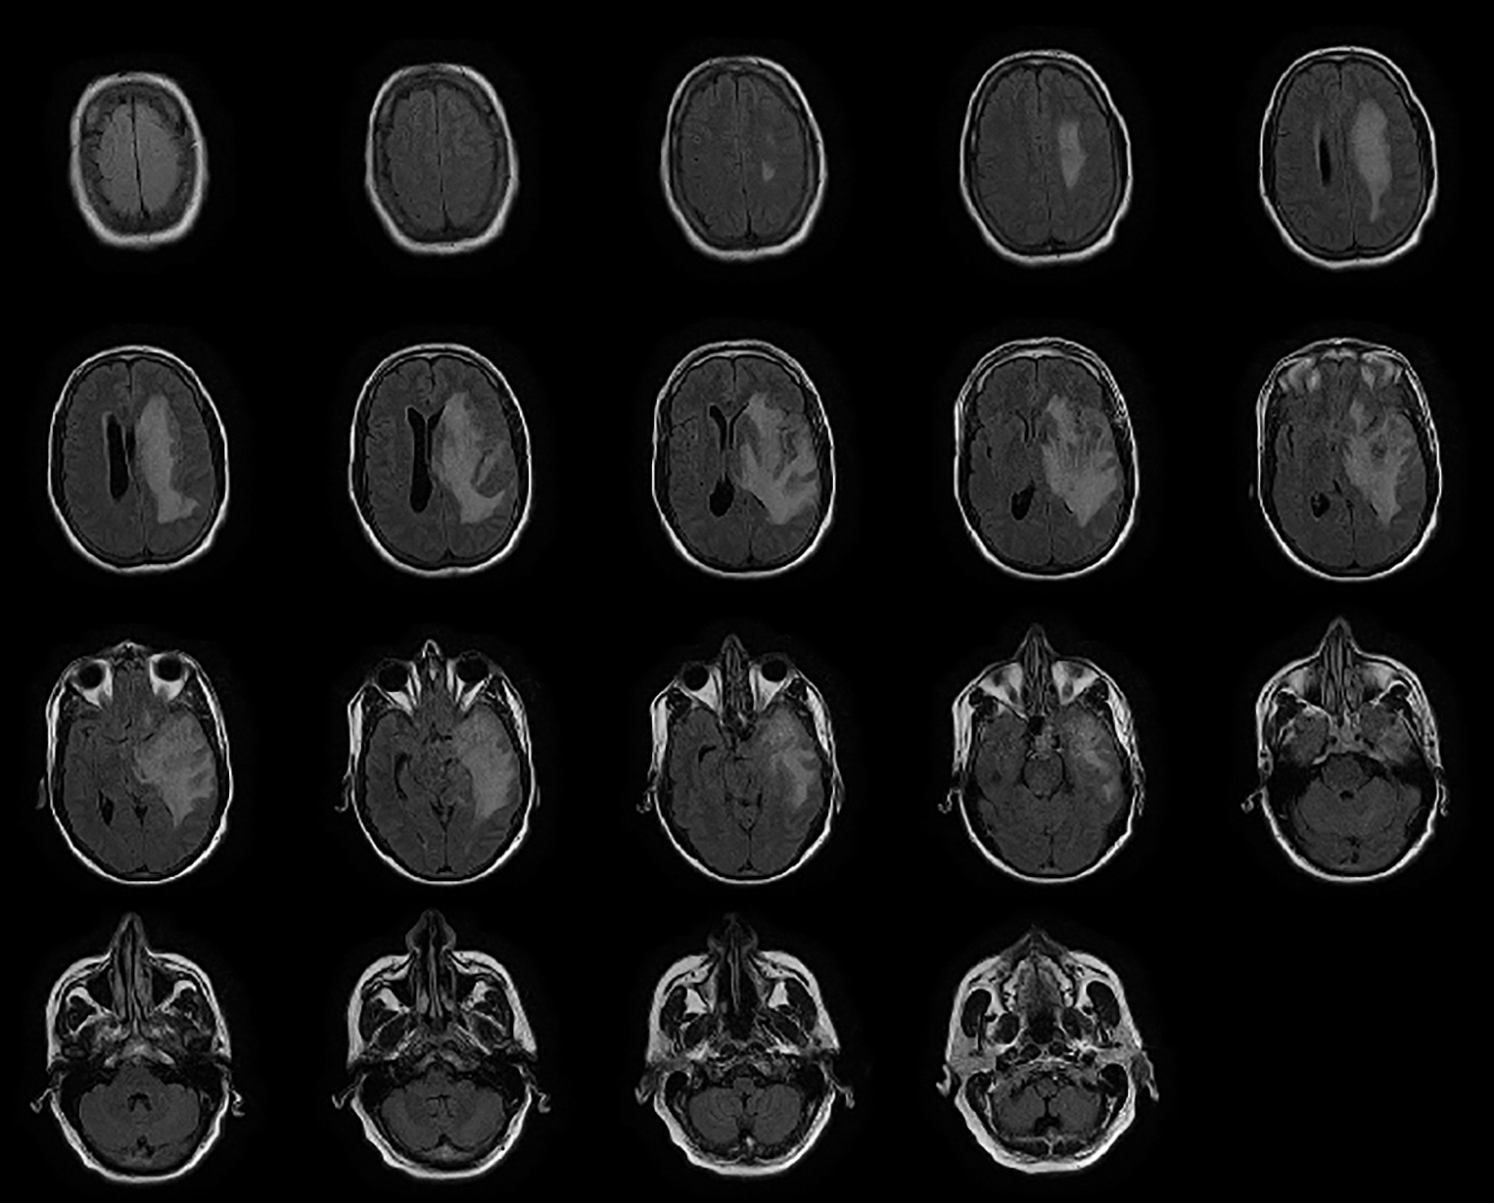

The patient's data utilized in this paper were collected from a medical institution's radiology department named Rahman Medical Institute (RMI) Peshawar, KPK, Pakistan. The collected dataset was then arranged in the form of a DICOM plan for classification. The distribution of images is shown in Tab. 1. Our collected dataset has a form of each 16 pieces with the level of pixels on the separation of the value 0.3875*0.3875 millimeters. In contrast, the widths of the data pieces were calculated at 6 millimeters. The dataset consists of T1-weighted (T1w) imaging [33]; tissues with short T1 appear brighter than tissues with longer T1, T2-weighted (T2w) imaging; tissues with long T2 appear brighter (hyperintense), and likewise as Fluid-attenuated inversion recovery (FLAIR) image having a center, coronal, and sagittal view. T1 and T2 are physical tissue properties (i.e., independent of the MRI acquisition parameters). For example, the gray matter has a T1 relaxation time of 950 ms and a T2 relaxation time of 100 ms (approximately, at 1.5 Tesla). The proposed system uses BX50 (40x strengthening aspect) for catching images from the dataset. The image is put away with no standardization and shading normalization to limit the intricacy and data misfortune in the investigation.

The preprocessing steps are utilized on the DICOM's datasets to improve the image value and outcome. The MR images are generally more challenging tasks to portray or assess because of their low-intensity scale. Also, the MR images may be dropped to a low level by such artifacts uprising from diverse resources, which can be considered significant to any process. Motion, scanner-specific variations, inhomogeneity are among the key objects that are seen in MR images. Fig. 2 shows how much the identical anatomical object is deriving and utilizing the exact procedure of the scanner. In addition, Fig. 2 also describes how much intensity value across the identical organ within the same patient, i.e., the fat tissue in Fig. 2, may vary in alternative locations. It is important to apply solid and effective procedures to prepare MR images for standardization, registration, bias field correction and denoises.

Figure 2: Northwest general hospital brain DICOM image dataset